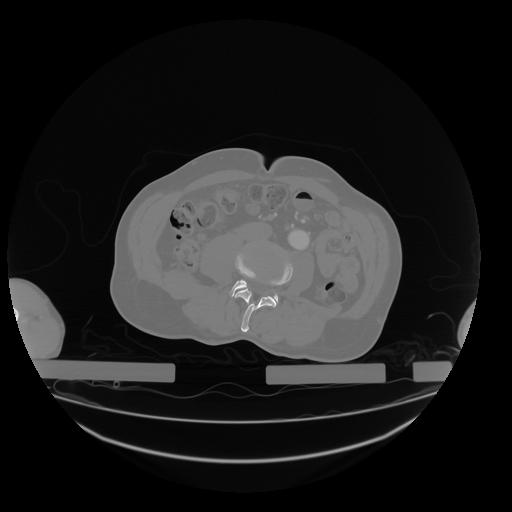

28 CUERPO,CE,Vol,2.0,CUERPO,,